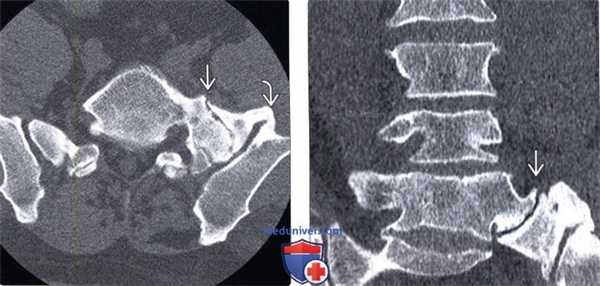

2. КТ при синдроме Бертолотти:

• Бесконтрастная КТ:

о Переходный пояснично-крестцовый сегмент с формированием блока или аномального сочленения между каудальным поясничным позвонком и крестцом/подвздошной костью

(Слева) КТ, аксиальный срез: наличие мощного мостовидного псевдосочленения между каудальным поясничным сегментом и крестцом и подвздошной костью слева, справа подобные изменения отсутствуют.

(Справа) КТ, фронтальный срез: массивный неоартроз между телом каудального поясничного позвонка и крестцом, сочленяющиеся поверхности отличаются неровностью контуров, в полости сочленения присутствует феномен вакуума.